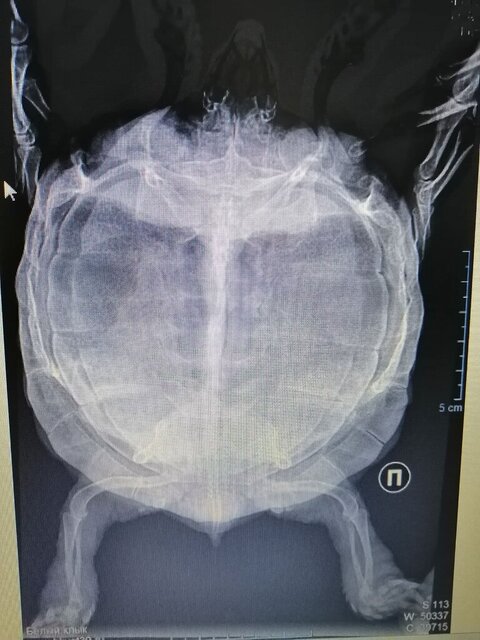

По вашему совету были на приёме у ветеринара в клинике,, Белый клык,, (теперь это,, БКвет,,). Сделали рентген.

Поставили предварительный диагноз Тимпания ЖКТ (желудок разбух). Липидоз печени под вопросом. Лечение - мелоксивет 0.2% по 0.05 мл пк 1 раз в день 5-7 дней. Мотилиум (не получается его дать!). Кормление принудительное в пасть (тоже не получается).